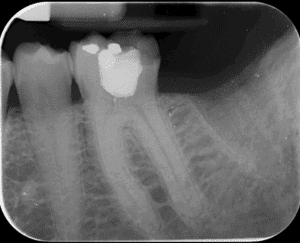

Figure 1 : Radiographie pré-opératoire d’une molaire mandibulaire présentant une nécrose pulpaire